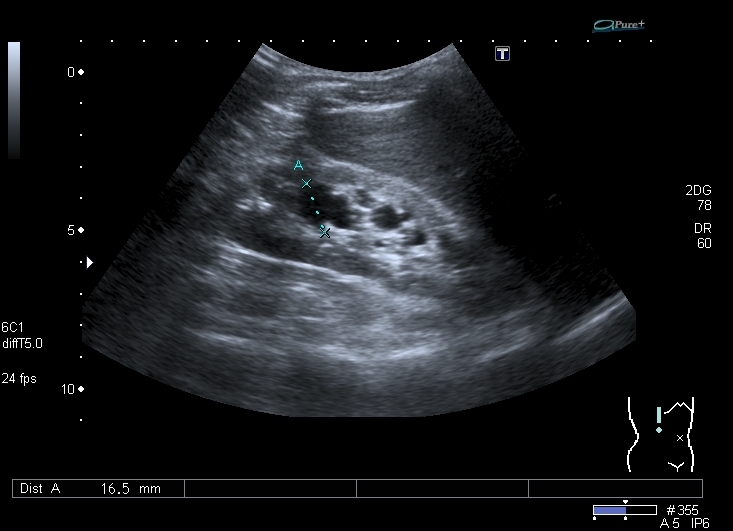

Добавляю ещё два скана, возможно не совсем классических

Есть ли классическая сонограмма этой почки (продольная, чтобы почка была бобовидной формы)?